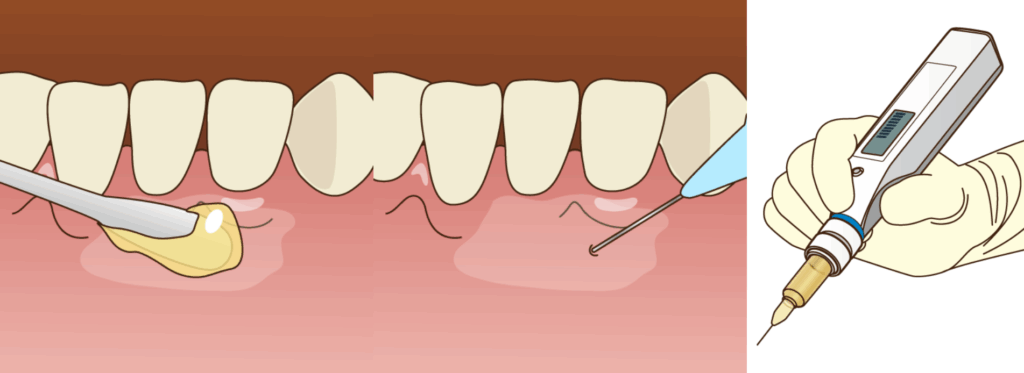

当院では麻酔の注射そのものの痛みを軽減するため、

- 注射を打つ部分の歯ぐきに、まず表面麻酔を塗布

- 国内でもっとも細いクラスの注射針を使用

- 一定の圧力でゆっくりと注入できる電動麻酔器を使用

といったステップを常に丁寧に行っています。

そして、麻酔が完全に効いていることを患者様ご自身にもご確認いただいた上で処置を開始しますので、ご安心ください。